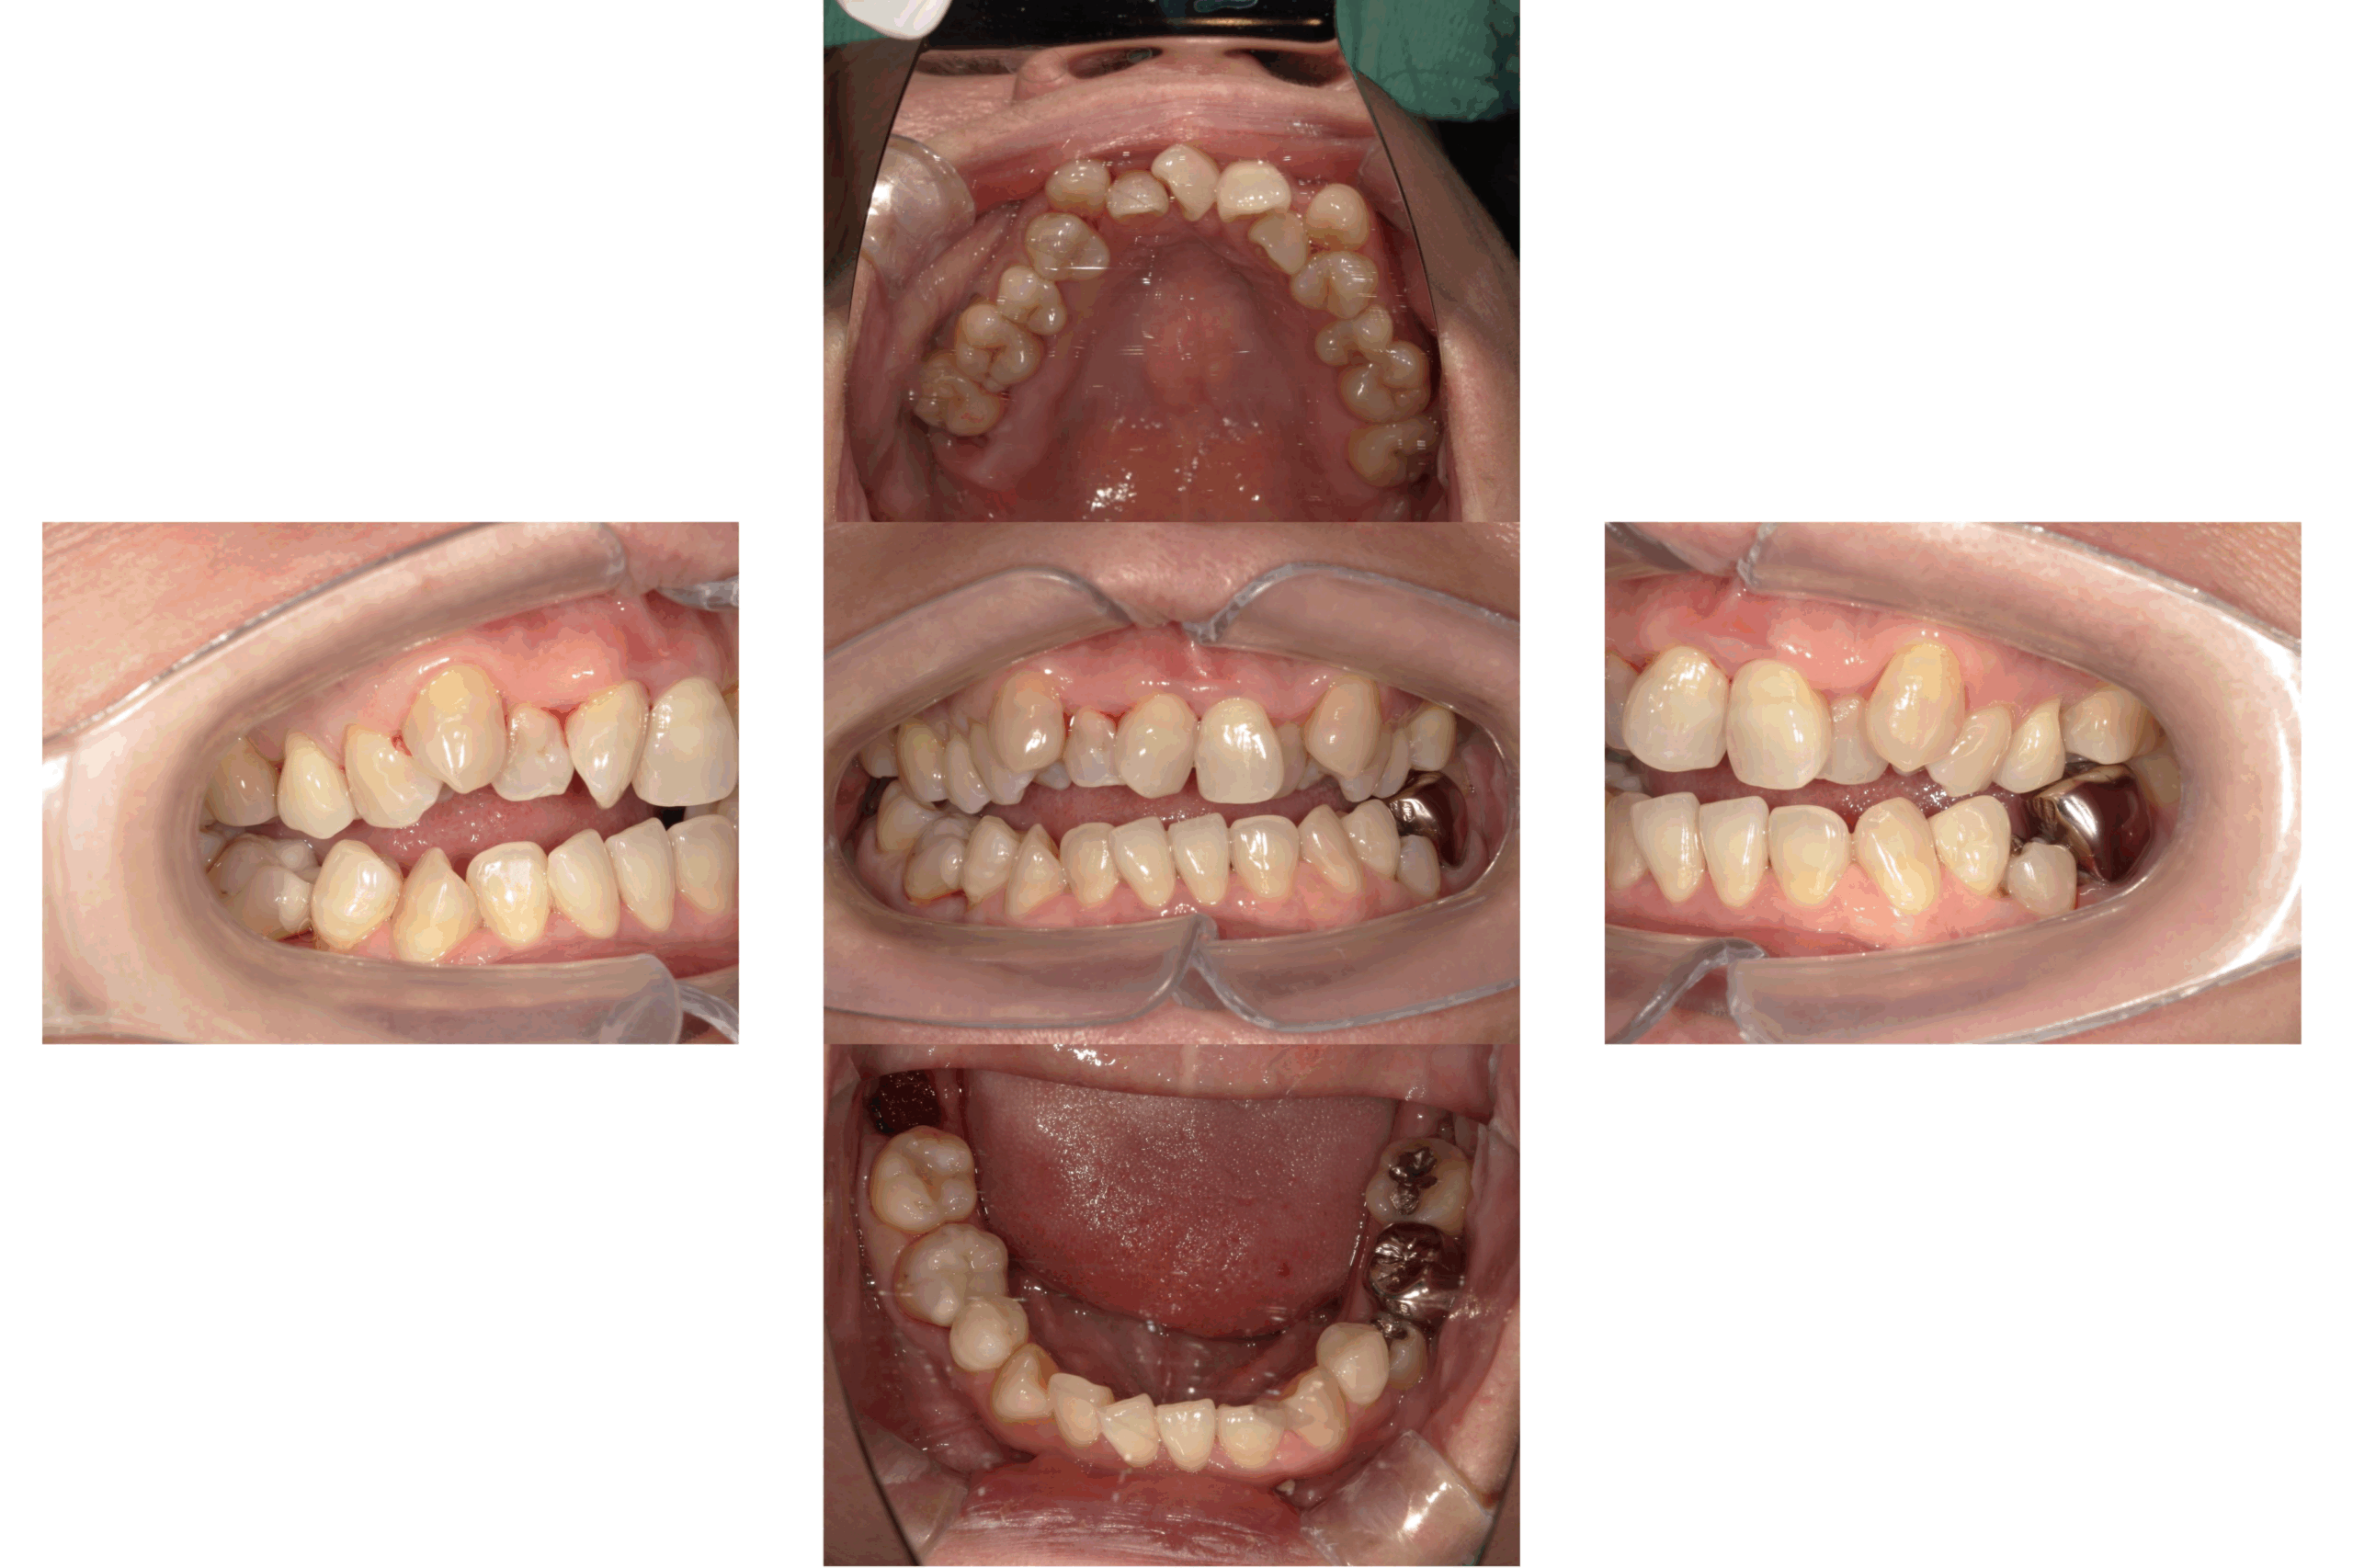

治療前

治療後

| 年齢 | 61歳 |

| 主訴 | 前歯でものが噛みきることが出来ない。歯の黄ばみも気になる |

| 治療期間 | 約2ヶ月 |

| 治療費 | 約750,000円 |

| 概要 |

前歯でものをしっかり噛みきれず、噛み合わせの改善に加えて、見た目の改善も希望されていました。また、歯の黄ばみが気になるとのことで、自然な白さと機能性を両立した治療をご希望されました。 |